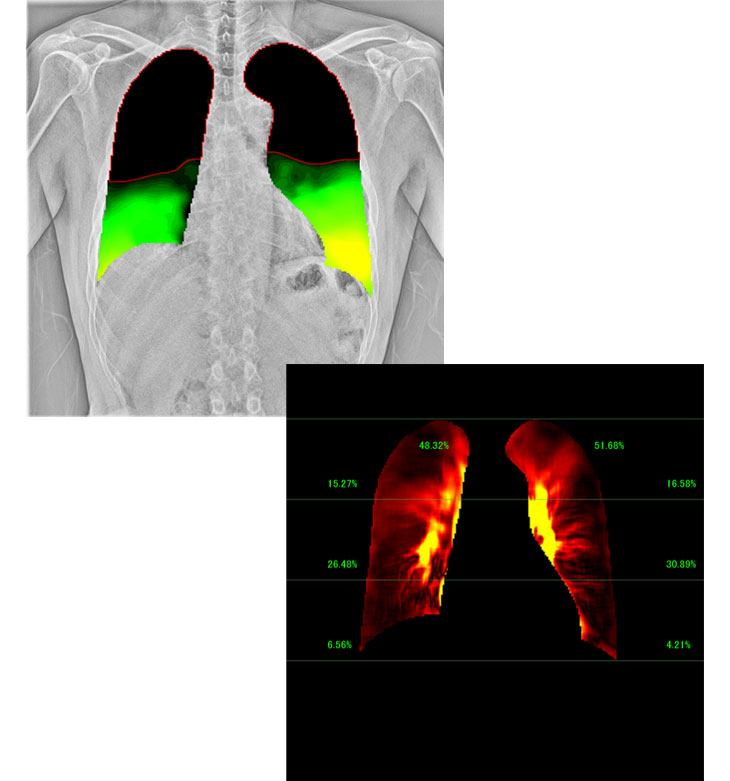

1. X線動画解析ワークステーション KINOSIS(キノシス)

単純X線撮影は、静止画から動画へ。コニカミノルタは単純X線撮影の常識である従来の静止画撮影に加え、動画撮影による新たな診断価値創出にチャレンジしています。X線動画解析ワークステーション『KINOSIS』は、臨床の現場で使用されることにより日々進化しています。動きの観察のしやすさを追求した新たな解析アルゴリズムの開発は、さらなる診断価値の向上や生産性の向上につながると考えています。変革に挑み続ける当社の技術をご体験ください。

8. 技術紹介 人工知能 (AI) 技術

X線動画解析、検診、画像検査を人工知能(AI)技術開発の重点領域として、臨床での利用に即した機能のご提案をしております。X線動画解析では、動き/機能解析の高度化による新たな診断価値、検診領域では、主要画像検査に対する効率化と早期検出、また、画像検査業務では、ワークフローの改善によるコスト削減を目指しており、将来の技術展示のコーナーで開発中の技術をご紹介します。